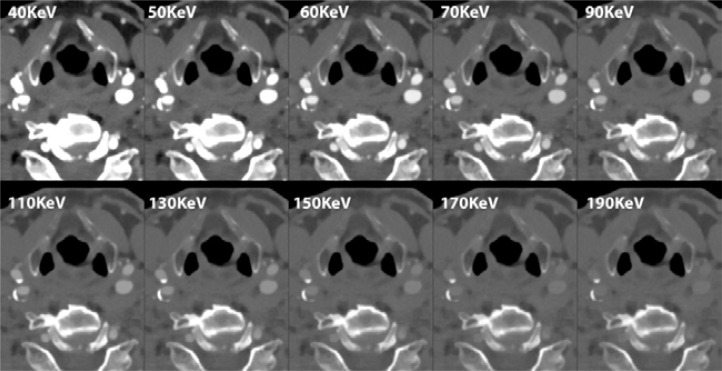

Photon-counting detector computed tomography (PCD-CT) devices have recently been introduced into practice, despite photon-counting detector technology having been studied for many years. PCD-CT devices are expected to provide advantages in dose reduction, tissue specificity, artifact-free imaging, and multi-contrast demonstration capacity. Noise reduction and increased spatial resolution are expected using PCD-CT, even under challenging scanning conditions. Some experimental or preliminary studies support this hypothesis. This pictorial review illustrates the features of PCD-CT systems, particularly in the interventional field. PCD-CT offers superior image quality and better lesion discrimination than conventional CT techniques for various conditions. PCD-CT shows significant improvements in many aspects of vascular imaging. It is still in its early stages, and several challenges have been identified. Also, PCD-CT devices have some important caveats. The average cost of these devices is 3 to 4 times higher than conventional CT units. This additional cost must be justified by improved clinical benefits or reduced clinical harms. Further investigations will be needed to resolve these issues.